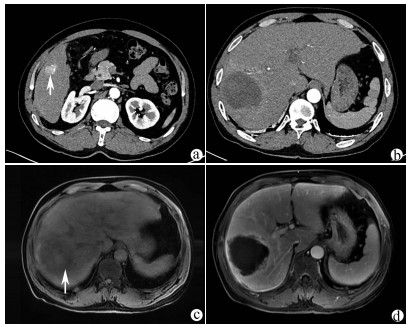

A case of Alagille syndrome

Shan TANG, Li BAI, Wenyan SONG, Chen LIANG, Jie BAI, Sujun ZHENG

2021, 37(9): 2185-2187. DOI: 10.3969/j.issn.1001-5256.2021.09.036

Abstract(964) HTML (503) PDF (2747KB)(57)

Abstract: